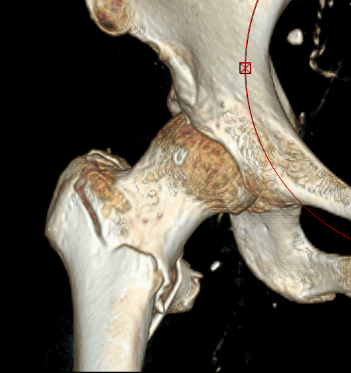

METHODS: A total of 21 hips were selected from 19 patients with osteonecrosis of the femoral head implanted with ceramic rods at the peri-collapse stage. Preoperative and postoperative imaging data were obtained, and relevant CT images were loaded in Mimics 21.0 software to construct a three-dimensional model of the femoral head. A global model of the proximal femur that includes cortical and cancellous bone, as well as a model of the proximal cancellous bone of the femur were created. The preoperative MRI image data of the patients were imported, and the necrotic lesion model was made by using the graphic matching technology, which was saved in .stl format. They were transferred to Geomagic 2012 software for smooth and precise surfacing processing. The ceramic rod was designed and modeled in SolidWorks 2021 software, and the relevant models were imported for assembly and Boolean operation. After ensuring that the interference check was correct, the stress and displacement of the weight-bearing area and necrotic area of the femoral head during the one-legged standing and walking post-pedal stages were calculated and observed by the ANSYS 2021 software.

RESULTS AND CONCLUSION: (1) The area of maximum stress on the femoral head was located above the anterolateral aspect of the necrotic part, and the stress values of the postoperative weight-bearing area and necrotic area were significantly lower than those before operation when standing on one foot (P < 0.05). The risk of femoral head collapse was lower than that before operation (P < 0.05). (2) In the postoperative pedaling stage, with the increase of the load, the stress values and collapse risk of the postoperative weight-bearing area and necrosis area increased, but they were still lower than those before the operation (P < 0.05). (3) Medullary core decompression combined with ceramic rod implantation can help to reduce the load on the weight-bearing area of the femoral head surface, so that the stress in the weight-bearing area can be effectively dispersed, and the load part is transferred to the direction of the femoral moment, which can improve the local stress concentration state and effectively support the femoral head to prevent further collapse.